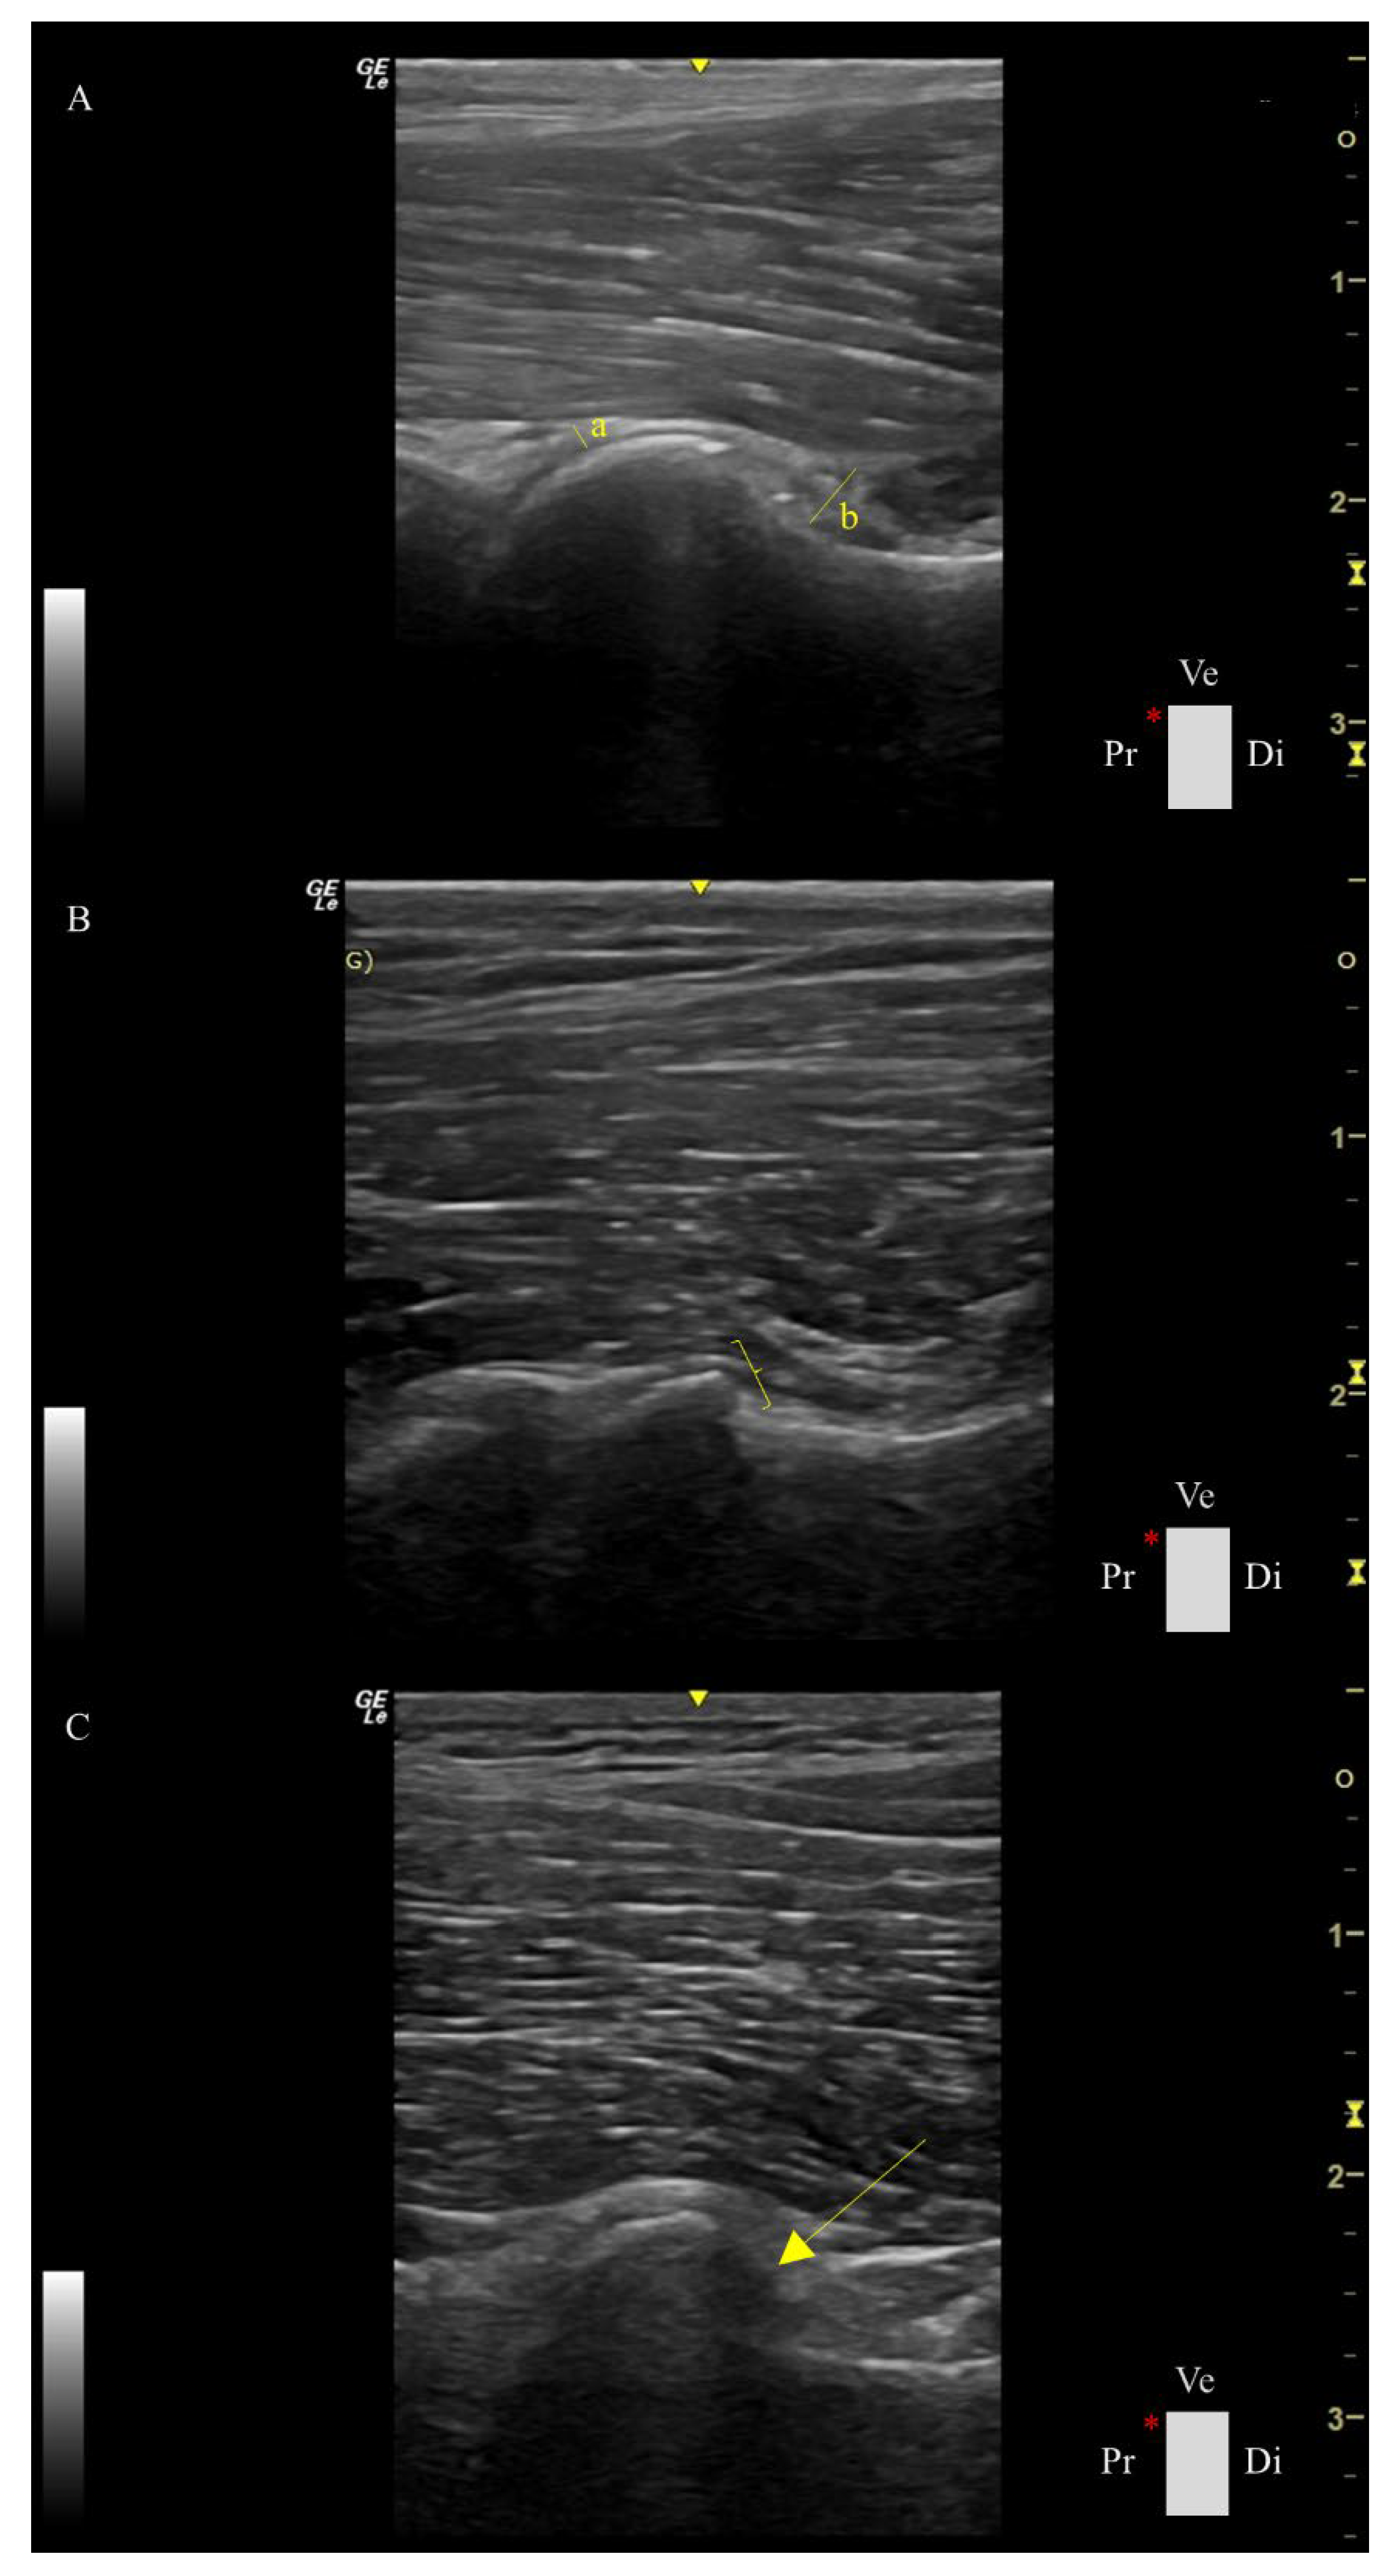

Ultrasound assessment was performed using a portable US machine (Logiq e, General Electric Medical Systems, Buc, France) equipped with a high-frequency linear probe (L8-18i-RS, General Electric Medical Systems, Buc, France) in a standardized ventral longitudinal approach to the femoral head-neck region, as described by Tomé et al. [17]. The following parameters were assessed for each hip as follows (Figure 1):

1. Capsule thickness at the femoral head index (CTFHi): measured in mm/ body weight *100. The capsule was measured as the maximum perpendicular distance between the external and internal limits of the joint capsule.

2. Capsular-synovial fold thickness index (CSFTi): measured in mm/ body weight *100, which comprises the perpendicular distance between the external limit of the outer synovial membrane layer and the internal limit of the inner synovial membrane.

3. Femoral head shape score (FHSs): spherical, flattened, or severely flattened was converted into a numerical scale of 1, 2, or 3, respectively.

4. Femoral head-neck transition score (FHNTs): smooth, irregular, or highly irregular was converted into a numerical scale of 1, 2, or 3, respectively.

5. Osteophyte score (Os): absent or present was converted into a numerical scale of 0 or 1, respectively.

Figure 1. Ultrasound parameters were performed in the longitudinal plane of the femoral head-neck plane. A: Hip of a dog with a capsule thickness at the femoral head (a) of 2.11 mm, measured at the maximum perpendicular distance of the joint capsule; a capsular-synovial fold thickness index of 8.32 mm (b), measured as the perpendicular distance between the outer and inner synovial membrane layers; with a spherical femoral head; a smooth head-neck transition score, and without osteophytes. B: Hip of a dog with a flattened femoral head, an irregular head-neck transition score (parentheses), and without osteophytes. C: Hip of a dog with a severely flattened femoral head, a highly irregular head-neck transition score, and the presence of osteophytes (arrow). Ve: ventral, Pr: Proximal, Di: Distal, Cr: cranial, Ca: caudal, and *: probe orientation and indication marker.